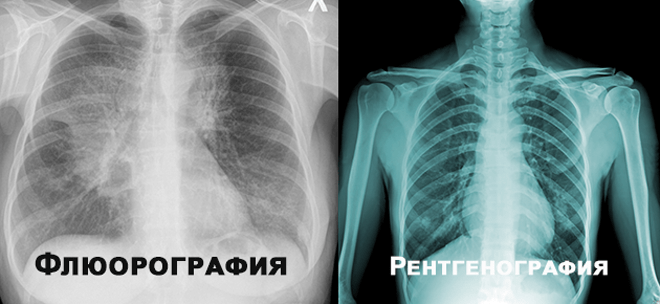

Чим відрізняється рентген від флюорографії: нюанси, які варто знати

- Деталізація зображення: Рентген — чіткіший, видно дрібні деталі, флюорографія — загальний огляд.

- Призначення: Рентген для точного діагнозу, флюорографія — для масового скринінгу легенів.

- Доза опромінювання: Зазвичай флюорографія має меншу дозу опромінювання, однак це сильно залежить від обладнання.

- Час обробки: Рентген займає більше часу, тоді як флюорографія швидше.